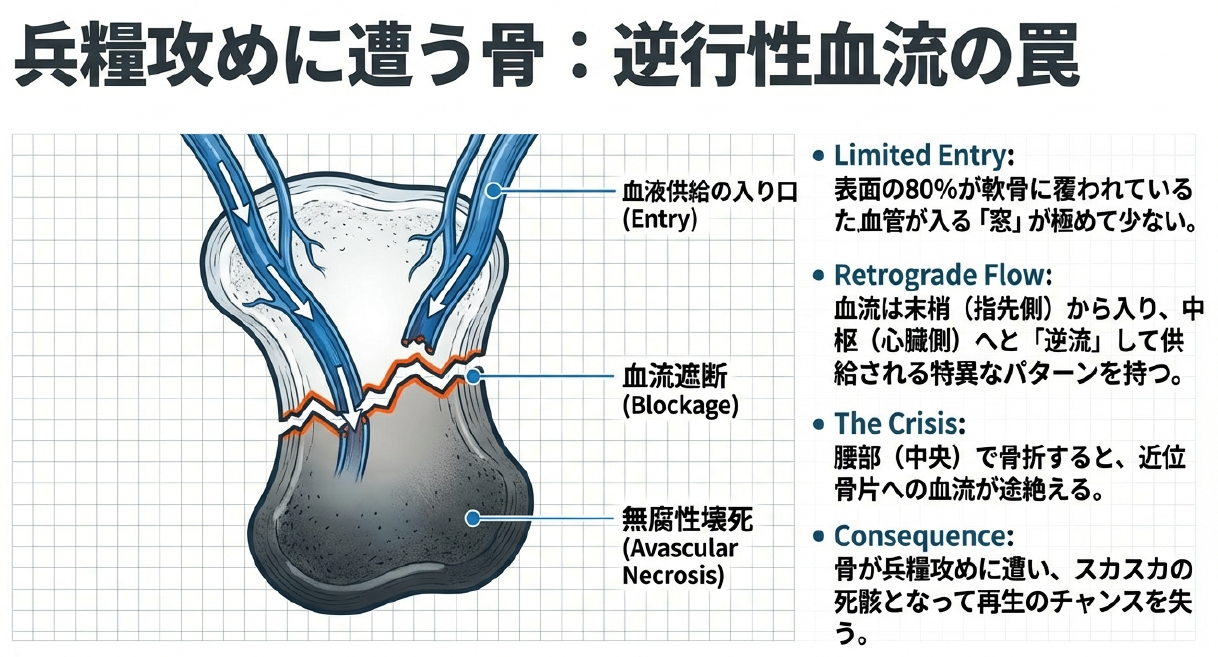

舟状骨骨折が「厄介」だと言われる最大の理由は、その血流支配の特殊性にあります。通常、多くの骨は周囲の軟部組織や骨膜から満遍なく血液供給を受けますが、舟状骨の表面の約80%は関節軟骨に覆われており、血管が侵入できる「窓」が極めて限定的です。さらに驚くべきことに、その血流は「逆行性」という特異なパターンを持っています。手首の末梢側から入った血管が、骨の中を遡るようにして近位側へと血液を送っているのです。そのため、骨の中央部で骨折が起きると、近位側の骨片は瞬時に兵糧攻めに遭い、血流が途絶えてしまいます。これが、医学界で恐れられる「無腐性壊死」のメカニズムです。血液が届かない骨は、再生のチャンスを失い、スカスカの死骸のような状態になってしまいます。